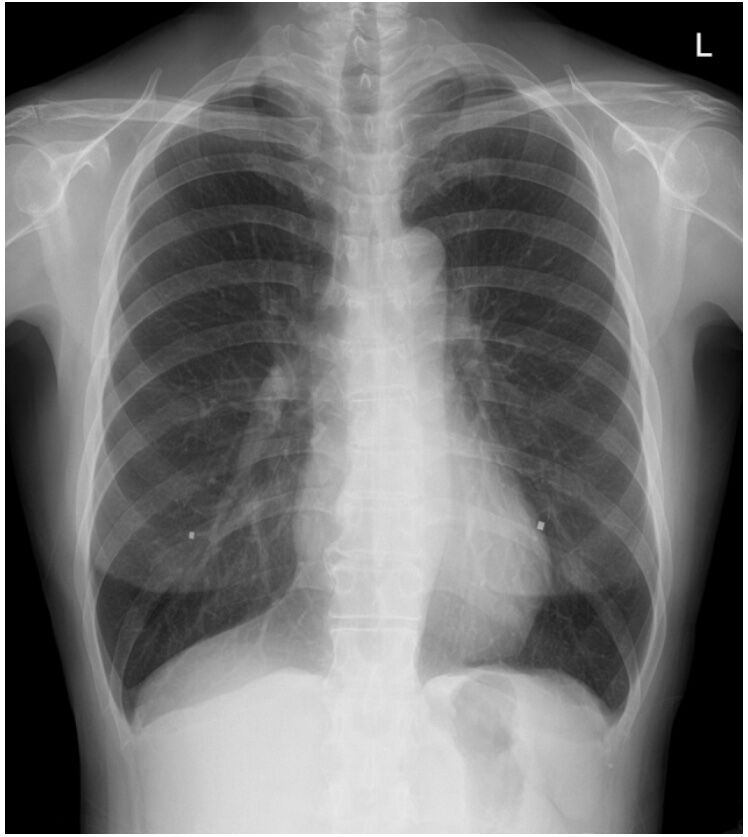

先生はレントゲン画像を見ながら、いつも通り大きな声で笑いながらおっしゃった。

「全然問題ないね。肺も、こんなに伸びてる。手術からどれくらいだっけ?」

「じゃあ、次はまた4ヶ月でX線。最近の調子はどう?」

会計でいつも通り支払いを済ませても、診察予定時間より早く終わった。支払額は、いつも通りの、医師診察料600バーツ(たった3分!)、診察パッケージ代350バーツ、X線650バーツ 合計1600バーツ(5,520円)。まあ、画像データはLineの受診記録からダウンロードもできるし、毎回先生の診断書も出してもらえるので、3分で何もかも終わるわけではないけれど。

現在の体調は4か月前の検診時と変化はない。でもこれを書きながら、もう2年が過ぎたのだと思った。私のがんはⅠAという初期で発見してもらえたので、転移や再発の可能性はほとんどないと言ってもらえた。でもほとんどないと言っても100%ないわけではない。ただ2年過ぎて、かなり気持ちが楽になっているのは事実だ。